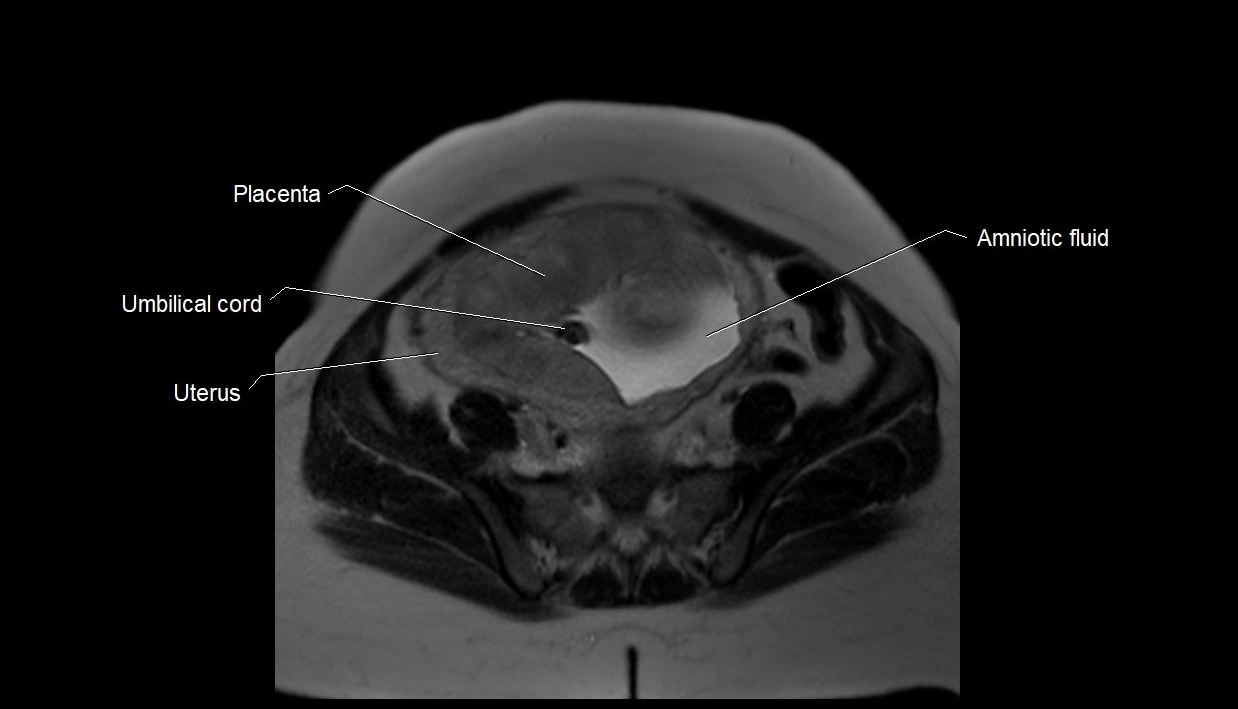

Amniotic fluid

Amniotic fluid is the protective liquid surrounding the fetus within the amniotic sac. It plays an essential role in cushioning the fetus, enabling fetal movement, maintaining temperature stability, and allowing for normal lung and musculoskeletal development.

The volume and composition of amniotic fluid change throughout pregnancy. It is mainly derived from maternal plasma in early pregnancy, while in later stages, it consists largely of fetal urine, lung secretions, and transmembrane exchanges.

MRI Appearance

T2 HASTE (T2 GRE):

• Amniotic fluid shows very bright hyperintense signal

• Provides natural contrast against fetus and placenta

• Small particles (vernix) may appear as scattered hypointense foci within bright fluid

T1 GRE:

• Amniotic fluid shows low signal intensity (dark)

• Hemorrhage, infection, or proteinaceous content may cause focal or diffuse high signal intensity